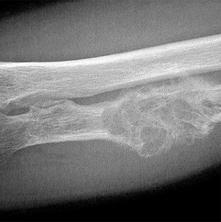

На рентгенограммах трубчатых костей можно увидеть бесструктурный очаг округлой или овальной формы, с склерозированными стенками, находящийся в области диафиза. При локализации в губчатых костях отмечается выпячивание кости и разрушение кортикального слоя.

На рентгенограммах можно увидеть участок деструкции с трабекулярной структурой. При поражении ребер или малоберцовой кости отмечается выпячивание кости. В длинных трубчатых костях характерно истончение кортикального слоя.